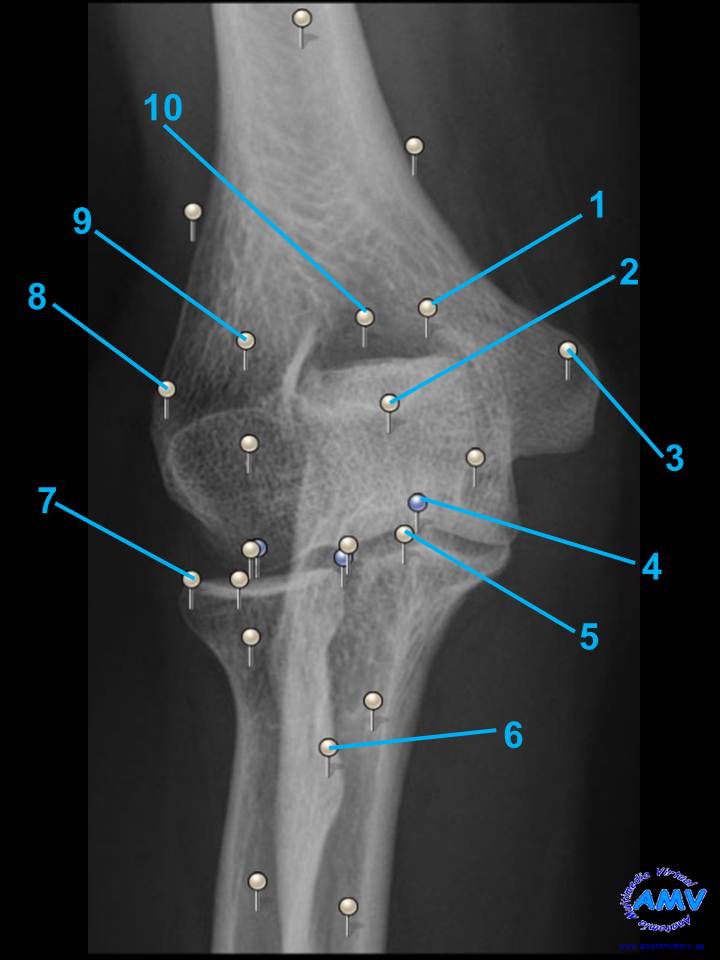

Radiografía del Codo I

rx_ms_07.jpgIndique que estructura se señala con el número correspondiente:

El nº 1 señala .

El nº 2 señala .

El nº 3 señala .

El nº 4 señala .

El nº 5 señala .

El nº 6 señala .

El nº 7 señala .

El nº 8 señala .

El nº 9 señala .

El nº 10 señala .